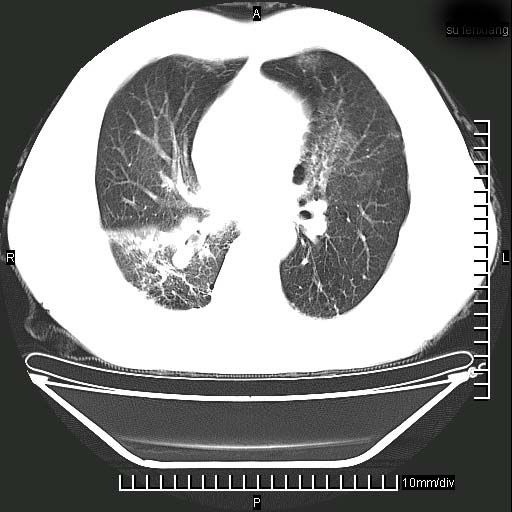

标题: CT24043:胸部增强:男性,60岁

既往肺结核,近10几天,咳嗽,咳痰,右侧胸痛,疼痛较明显,右上肺斑块考虑结核灶胸膜粘连,增强,可惜动脉期没有定好,未见强化,可延迟4分后又见较明显强化,中心见低密度影,如果说结核是边缘强化,可这个灶强化的面积挺大的,让人很挠头。

1)两肺继发性肺结核。2)右侧胸膜增厚+少量胸腔积液。